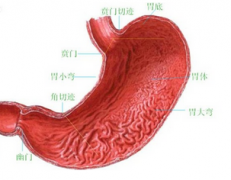

肠胃炎是什么病?

导语 盘锦医生表示:肠胃炎是胃黏膜和肠黏膜发炎,通常因微生物感染引起。

肠胃炎该如何诊断?

导语 肠胃炎是临床很常见疾病,朋友们在日常生活中如果不注意饮食,很容易

肠胃炎怎么治疗好?

导语 肠胃病是属于人体消化道疾